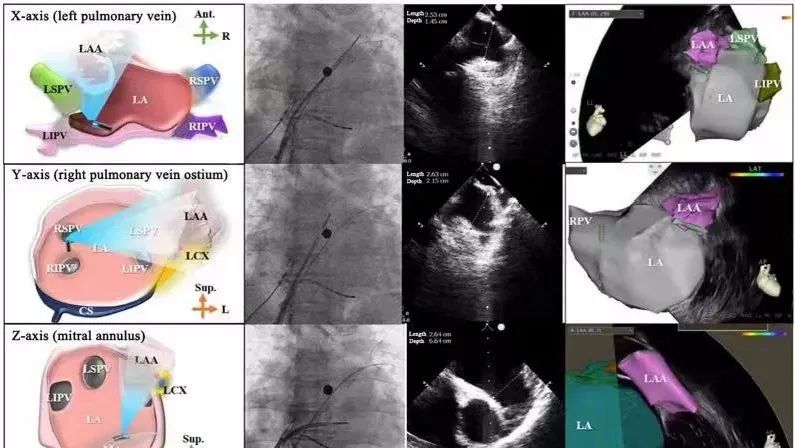

一種與心導(dǎo)管檢查相結(jié)合的超聲心動圖診斷新興技術(shù),通過將超聲探頭置于心腔內(nèi)部,發(fā)射并接收超聲信號,來精確獲取心臟解剖結(jié)構(gòu)、心臟血流動力學(xué)等信息的實時成像。與其他影像技術(shù)相比,ICE技術(shù)具有操作簡單、無輻射、安全性高、手術(shù)效率高、實用等優(yōu)勢,ICE在很大程度上有望取代經(jīng)食道超聲心動圖(TEE),成為電生理和結(jié)構(gòu)性心臟病領(lǐng)域的理想成像方式。

目前ICE技術(shù)已被應(yīng)用于左心耳封堵、房顫射頻消融、二尖瓣成形、房間隔缺損封堵等多種心臟介入手術(shù),應(yīng)用場景主要圍繞臟電生理、結(jié)構(gòu)性心臟病等領(lǐng)域,目前以電生理應(yīng)用為主。數(shù)據(jù)顯示,我國結(jié)構(gòu)性心臟病介入器械市場規(guī)模已從2017年的4億元增長至2021年的20億元,年復(fù)合增長率達48.3%;預(yù)計到2025年,該市場規(guī)模將達到104億元,可以預(yù)見ICE市場規(guī)模也將同步高速增長,未來市場發(fā)展空間廣闊。

心腔內(nèi)超聲(ICE)技術(shù)壁壘極高,國內(nèi)主要廠商核心部件仍舊為進口,集成了超聲和圖像處理最前端技術(shù),包括超聲探頭、線纜、軟件成像算法等,是當前內(nèi)窺超聲方向最具挑戰(zhàn)的領(lǐng)域。ICE的應(yīng)用經(jīng)歷了2D平面成像、3D三維立體成像、以及4D的實時三維立體成像階段。